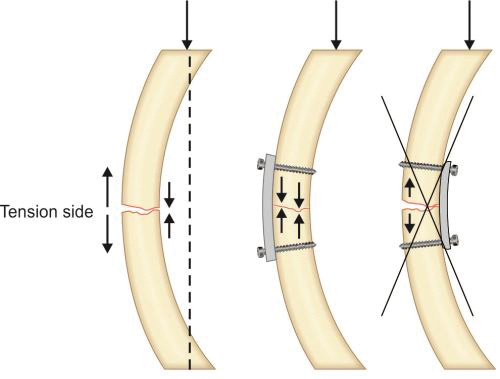

-

The tension band principle: Tensile/distractive forces are converted into compressive forces by applying device (either plate or tension band wire) on convex surface or tension surface of a fractured bone (Fig. 1.43). Here the patellar fragments are being distracted by quadriceps above and ligament patellae below. A wire has been tied on the convex side of patella. This will get stretched due to patellar distraction by quadriceps and just like a stretched rubber band it will reciprocally exert compression pull upon this stretch to compress the fracture (Newton's third law of motion).

Fractures where tension band principle is commonly used are listed in Box 1.11.